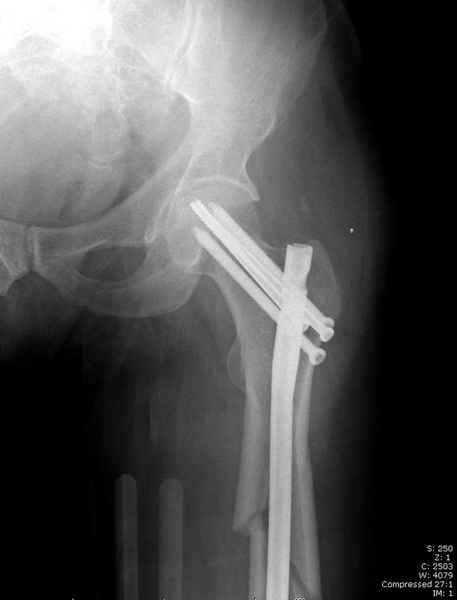

Среди русскоговорящих коллег Ортофорум стал одним из мест, где многие из нас черпают знания для решения своих ежедневных проблем в виде практических советов и обмена опытом. Кроме таких советов, Ортофорум стал источником новых познаний среди ортопедов, особенно по редко встречающимся состояниям в ортопедии. Продолжая традицию, я хотел бы представить редко встречающий случай перелома бедра у больного с гемофилией. Больному 42, гемофилия типа А, из истории упал с высоты около 1,5 метра, переправлен из другой больницы. По происхождению мексиканец, 10 лет назад по поводу артроза пр. коленного сустава в Мексике сделано протезирование, которое закончилось ампутацией выше коленного сустава. При поступлении бедро напряженное, сосудистых и неврологических расстройств нет. На рентгенограмме оскольчатый перелом бедра с вовлечением проксимальной спирали в шейку бедра. Хотели бы знать тактику ведения подобных больных и на что надо обратить внимание? Djoldas Kuldjanov, MD Department of Orthopedic Surgery St. Louis University Medical Center

Учитывая, что случай ургентный, больной поступил вечером, не стали делать вытяжение и срочно провели операцию по фиксации перелома бедра антеградным штифтом Versa Nail от DePuy.

Для профилактики дальнейшего раскола в шейке предварительно во время проксимального рассверливания спереди и сзади провели временные спицы, которые в дальнейшем были заменены на шурупы (miss nail method)